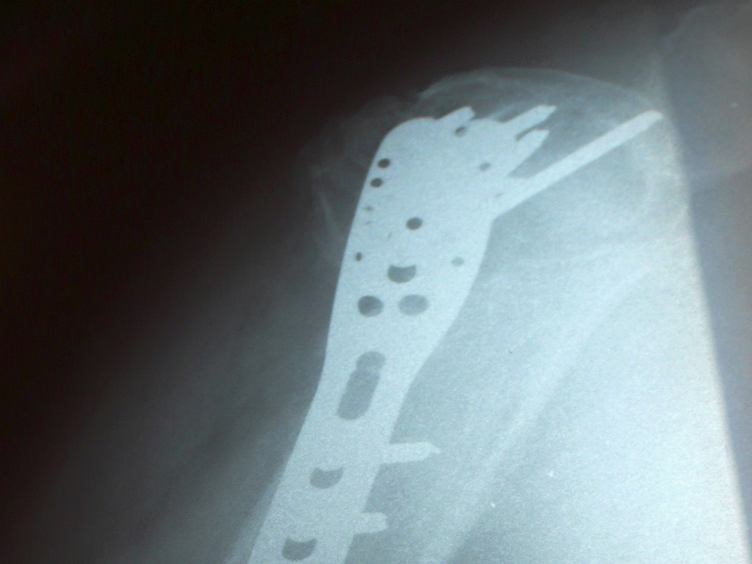

Jak teď mám ty střevní potíže, tak mám pořád chuť na čokoládu. Venku podle očekáváni nasněžilo. Velikonoce se blíží, zkouším něco nafotit. Mám ten pažit nějaký řídký, ale už se do něho sbíhají kuřata. Za chvilku nebude pro sama kuřata kam plivnout. Jedu do Orlové, táta má kontrolu ruky. Vyhrabáváni auta ze sněhu jsem už nečekal. Tátova ruka není pořád nic moc, ale je to teprve šest týdnů od operace. Na rentgenovém snímku je krásně vidět, jaké železářství má v rameni. Výsledkem kontroly je, že začnou rehabilitace. V orlovské nemocnici je to dnes naprosto děsné. Měl jsem dojem, že na ortopedickém oddělení je čistota naprosto nezbytnou podmínkou. Tady za provozu probíhají stavební úpravy. Špína, prach a hluk. Moc se nedivím, že i lékaři jsou dnes značně nevrlí. Mám toho docela dost a zbytek odpoledne prospím. Večer šmíruji, co se děje před domem, třeba jak sousedi zajíždějí do garáže nebo autoškolu, jak se učí rozjíždět do kopce. Ukončím to přáním, ať ta zima jde konečně do háje.